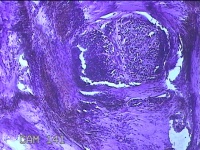

右侧中指尺侧包块

性别

女

年龄

53岁

临床诊断

肌腱腱鞘囊肿

一般病史

发现右侧中指尺侧一包块1年余,无明显疼痛及不适。

标本名称

大体所见

灰白暗红色肿物1.2x0.8x0.3cm一个,表面糜烂,切面灰白粉红色,质软。